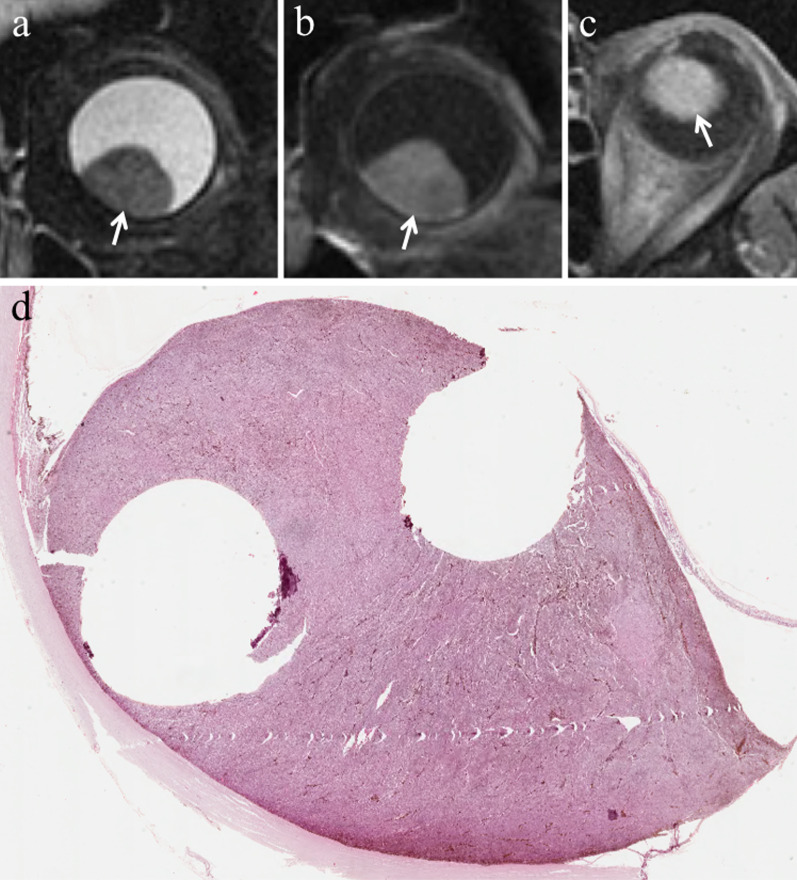

Fig. 7.

A 77-year-old man with a pigmented choroidal melanoma and hemorrhagic retinal detachment of the right eye. Axial (a) T2-weighted turbo spin-echo STIR and (b)( fat-suppressed T1-weighted images demonstrate an intraocular mushroom-shaped lesion along the postero-medial aspect of globe (white arrows). The mass exhibits the typical low signal intensity (lower signal intensity than vitreous body) on T2-weighted image and high signal intensity (higher signal intensity than vitreous body) on T1-weighted image. Along the postero-lateral aspect of globe, the hemorrhagic retinal detachment is better depicted on fat-suppressed T1-weighted image in which it displays high signal intensity due to subacute blood products (white arrowhead in b). (c) Histological examination: low magnification confirming the radiological finding of an intensely pigmented mass protruding from the postero-medial ocular wall (H&E, original magnification ×25). (d) The postero-lateral retinal detachment is also well documented at histological level (H&E, original magnification ×50)

In approximately 65% of patients, tumor growth determines retinal detachment, consisting in the split between the inner neurosensory retina and the underlying outer retinal pigment epithelium. Retinal detachment is deemed a manifestation of disease progression, although it is also related to individual factors. Retinal detachment has a typical imaging appearance showing a biconvex lentiform shape and a V shape with the vertex in correspondence of the optic nerve head and the extremities in the direction of the ora serrata (Fig. 14). This characteristic guise is due to anatomical reasons, as a consequence of retinal fastening to the flat portion of the ciliary body and to the optic nerve head [51]. When retinal detachment occurs, subretinal effusion can be: (a) exudative or serous, (b) hemorrhagic [47, 61], with signal intensity varying based on its protein content. Regardless of the kind of subretinal effusion, the retinal detachment is usually better demonstrated on T1-weighted sequences [23].

A 41-year-old woman with a pigmented choroidal melanoma and serous retinal detachment of the right eye. Axial (a) T2-weighted turbo spin-echo STIR and (b) contrast-enhanced fat-suppressed T1-weighted images show a pigmented choroidal melanoma along the lateral aspect of globe (white arrows); the lesion appears hypointense on T2-weighted image and hyperintense on contrast-enhanced fat-suppressed T1-weighted image. Along the posterior aspect of the globe a retinal detachment is hardly detectable on T2-weighted image, whereas it is better appreciable on fat-suppressed T1-weighted image (white asterisk in b) in which it does not enhance and demonstrates the typical biconvex V shape with the vertex in correspondence of the optic nerve head (white arrowhead). (c, d) Histology from a different patient from the one shown in MR images. The biconvex V-shaped retinal detachment, caused by a nearby intensely pigmented uveal melanoma, is readily identifiable on both (c) low (H&E, original magnifications ×25) and (d) high (H&E, original magnification ×50) magnification. Note the emergence of the optic nerve forming the vertex of the “V” (H&E, original magnifications ×25× and ×50, respectively)

To discriminate melanoma from retinal detachment is important in order to perform as reliable as possible tumor size measurements that have crucial implications in treatment planning and follow-up evaluation. Both Gd-based contrast agents and DWI are useful to distinguish retinal detachment from melanoma. In fact, uveal melanoma enhances and demonstrates restricted diffusion, whereas retinal detachment does not enhance and does not show restricted diffusion, unless hemorrhagic [26]. Only in this latter case retinal detachment may exhibit slight diffusion restriction and high signal intensity on T1-weighted sequences, because of subacute hemorrhagic content and paramagnetic effect of methemoglobin with T1 shortening (Figs. 7b, 15 and 16) [26]. For this reason, hemorrhagic retinal or choroidal detachment may also mimic melanoma at MRI [53]. The mean ADC of retinal detachment is 1986 × 10–6 mm2/s [59].